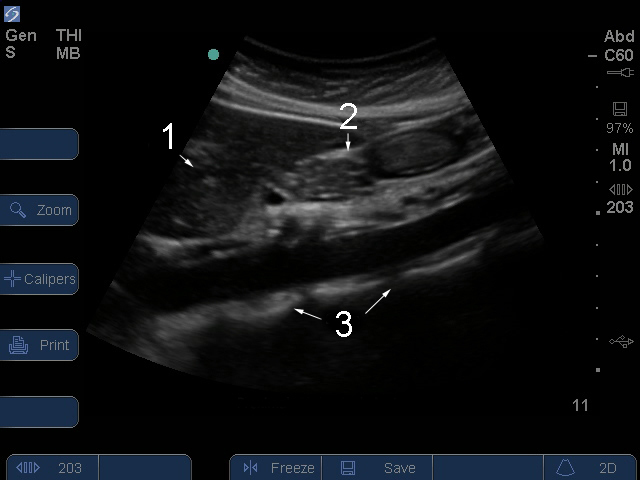

Serie S: Imagen sagital 2 de aorta proximal

Aorta abdominal proximal

Hígado

Páncreas

Columna